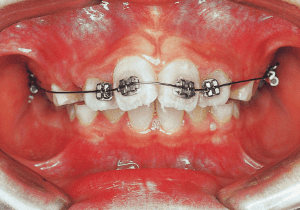

2 After Phase 2 Treatment 6-6-’94

The first phase of treatment involved extracting the left and right maxillary deciduous canines. The space created was used to forcibly retract the four anterior teeth, thereby aiming to improve lip closure function (6–9, 11). Morphological changes suggest that lip function differed before and after treatment (6, 9). Subsequently, the first premolars erupted, but extraction is planned to secure space for canine eruption (10). A Class II molar relationship remains, but the significant overjet has improved (11).